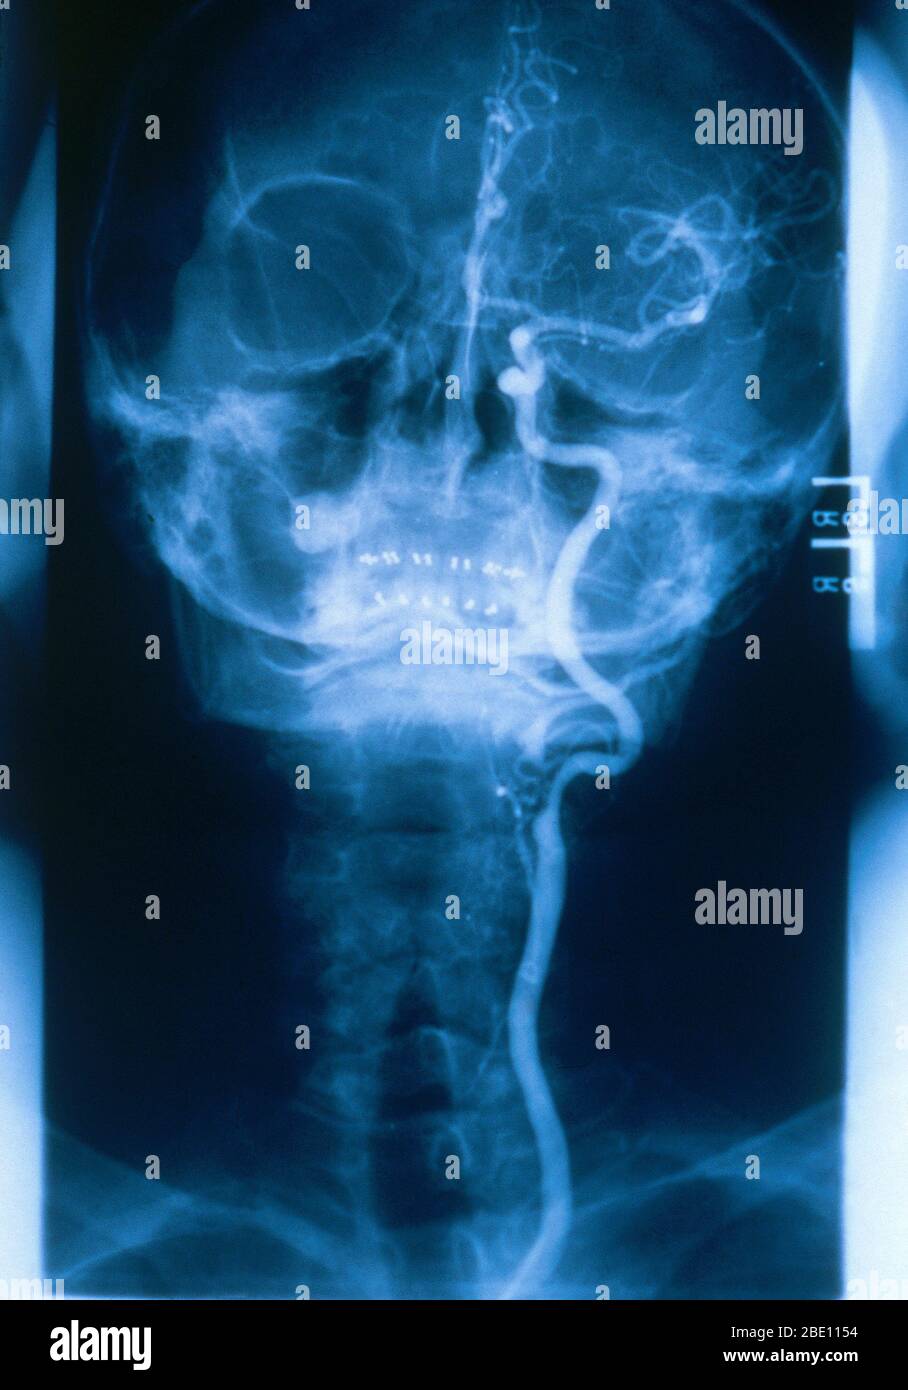

RM2BE1154–Medizinische Radiologie mit einem normalen linken Halsschlagader. Die gemeinsame Halsschlagader versorgt Hals und Kopf mit sauerstoffreichem Blut.

RM2BE0J9D–Medizinische Radiologie mit einem normalen linken Halsschlagader. Die gemeinsame Halsschlagader versorgt Hals und Kopf mit sauerstoffreichem Blut.